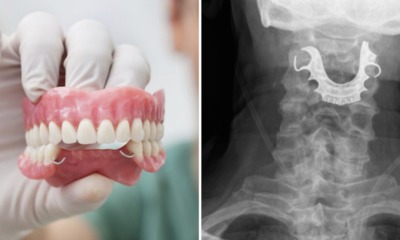

A doctor in Jakarta got a huge surprise when she took an x-ray of one of her patients recently. As reported by Indonesian news portal Detik,...